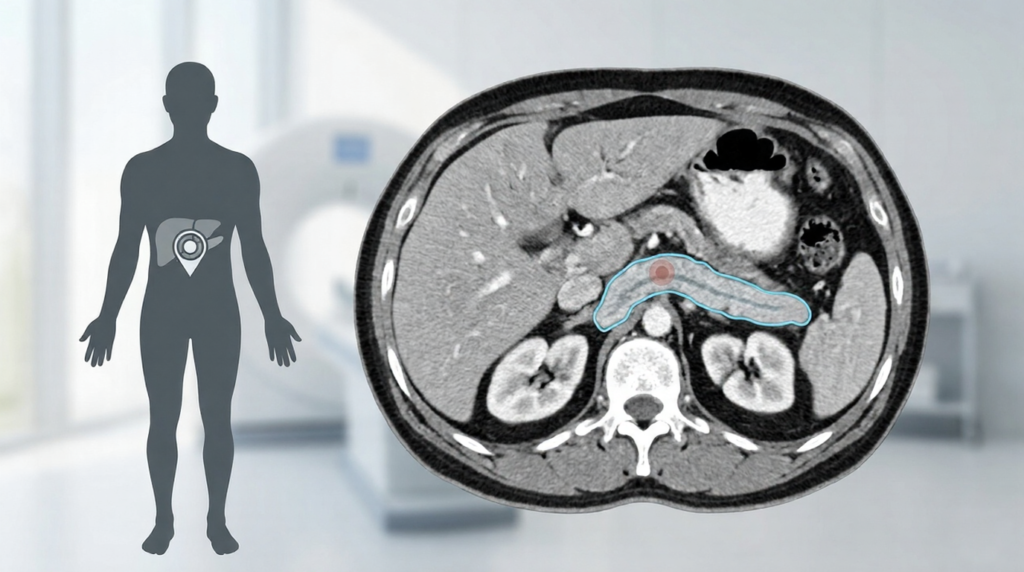

췌장암 검사 보험 적용 여부가 궁금하신가요? 실손의료비와 암보험 보상 기준, 입원 검사 팁과 필수 서류까지 현직 대학병원 간호사가 상세히 정리해 드립니다.